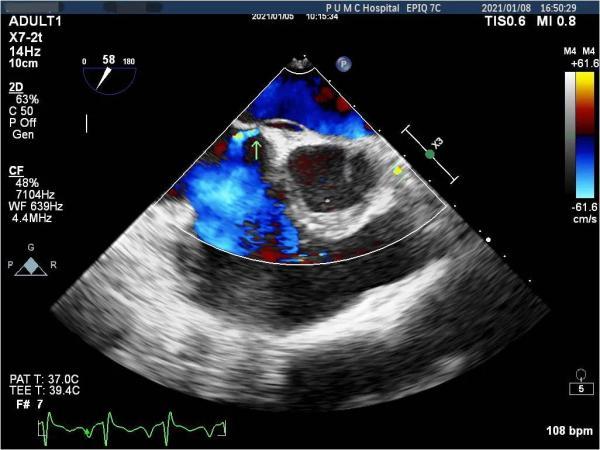

为进一步找寻病因 , 解除病痛的折磨 , 李女士于2020年12月慕名来到北京协和医院就诊 。 心内科主任荆志成教授接诊后 , 为患者安排了经食管超声心动图(TEE)检查 , 发现心脏房间隔存在左向右分流的血流 , 进一步行经颅多普勒超声(TCD)发泡试验 , 结果为阳性 , 确诊李女士有卵圆孔未闭 , 引发脑梗死的“元凶”被找到 。

【卵圆孔|攻坚克难|青年脑梗死竟因心脏有个“洞”!协和心内科成功补心】术前经食管超声心动图检查发现房间隔有卵圆孔未闭 , 且存在左向右分流 。